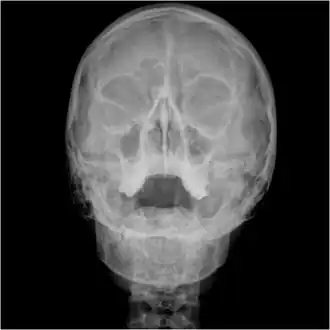

Waters view showing diffuse prominent mucosal thickening in the right maxillary sinus and mild nmucosal thickening in the left maxillary sinus.

An orbital x-ray usually requires only one view unless the requester is looking for evidence of metallic fragments, in which case two projections can be made. One with the eyes looking up, one with the eyes looking down. These views will show any movement of fragments and helps rule out false positives / artefacts which may be present on the image receiver. Two other important views are the Water's view which helps visualise the anterior orbital floor and maxillary sinuses; and the Caldwell view which helps to visualise the frontal and ethmoid sinuses and posterior orbital floor.[3]